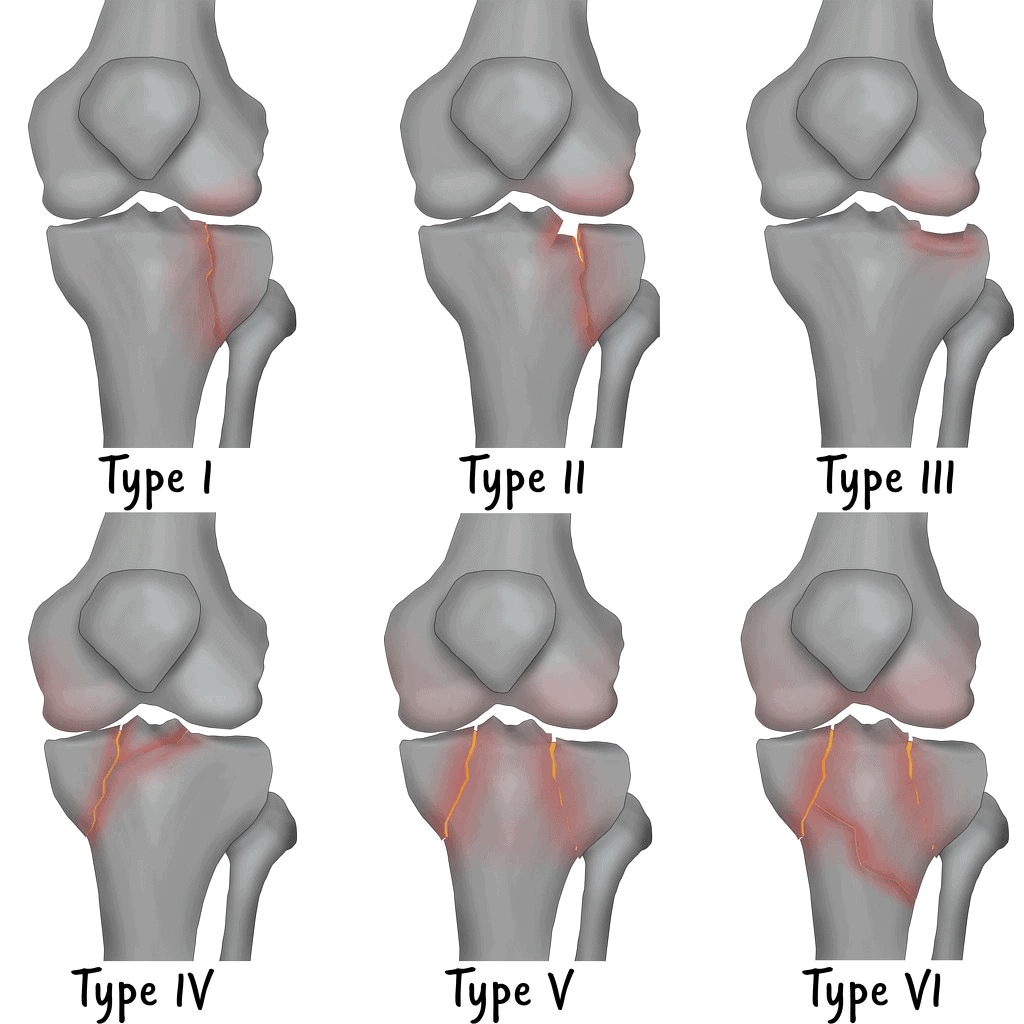

– Khớp gối bao gồm phần dưới của xương đùi và phần trên của xương chày (được gọi là mâm chày), đầu trên xương mác và xương bánh chè. Đầu xương được bọc bởi lớp sụn khớp. Một lớp sụn đệm vào giữa chúng gọi là sụn chêm trong (hình chữ C) và một lớp sụn bên ngoài gọi là sụn chêm ngoài (hình chữ O).

* Tibial plateau fractures: Review of the classification systems, management, and outcome – S. L. Coleman, R. Parisien, A. Guermazi, A. Murakami; Boston, MA/US

* Radiological classification of tibial plateau fractures: A pictorial essay – M. Winkel; QLD/AU

* The role of CT and MRI in the assessment of tibial plateau fractures according to Schatzker classification – I. Tsifountoudis, M. D. D. Sidiropoulos, I. Kalaitzoglou

* Tibial plateau fractures in CT : What the radiologist needs to know – H. ELASSAAD, N. Touil, O. Kacimi, N. Chikhaoui; CASABLANCA/MA